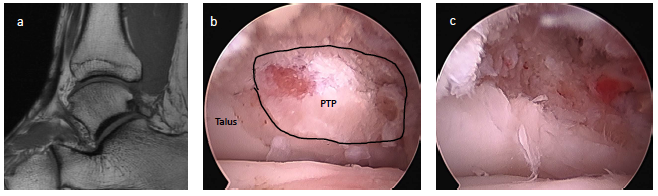

Posterior ankle impingement in athletes is often related to a previous sprain.7,11,12,15,16 Many times, soldiers who sustained syndesmosis injuries can develop a combination of soft tissue impingement lesions not only anteriorly but posteriorly as well (see first photo set above). We also see clicking, popping and snapping of the posterior tibiofibular ligament and posterior talofibular ligament in these cases. In a sense, we can see a posterior pseudo-version of Bassett’s ligament although this is not named as such. Whether this is a fraying of the ligament which now impinges on the posterior tibial lip or a true accessory ligament is not well-defined. Regardless, the imaging is often clear on MRI and intra-operatively (see second image set above). Almost every author states that symptoms always or only occur with plantarflexion, but I tend to see far more soldiers and athletes complaining of pain with dorsiflexion. To me, pain with stretching of the posterior capsule and distraction of the offending tissue makes far more sense that hurting with only plantarflexion.